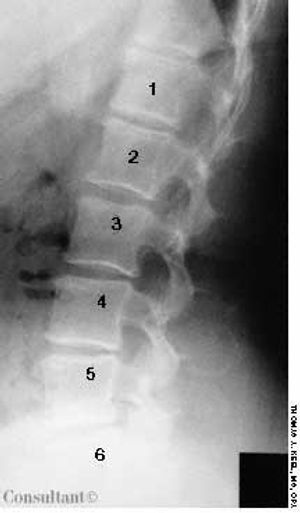

The wife of an 82-year-old man with Alzheimer's disease was concerned about her husband's poor posture. According to the woman, the patient had never sustained a back injury and had always maintained a sedentary lifestyle. He never smoked cigarettes and did not use alcohol. His history included multiple transient ischemic attacks (TIAs).